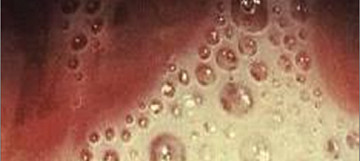

При подозрении на наличие папиллом в уретре гинеколог или уролог может провести визуальный осмотр с использованием специального увеличительного стекла или колпоскопа. Во время осмотра врач обращает внимание на наличие папиллом или других аномалий на слизистой оболочке уретры. - Различные тесты: